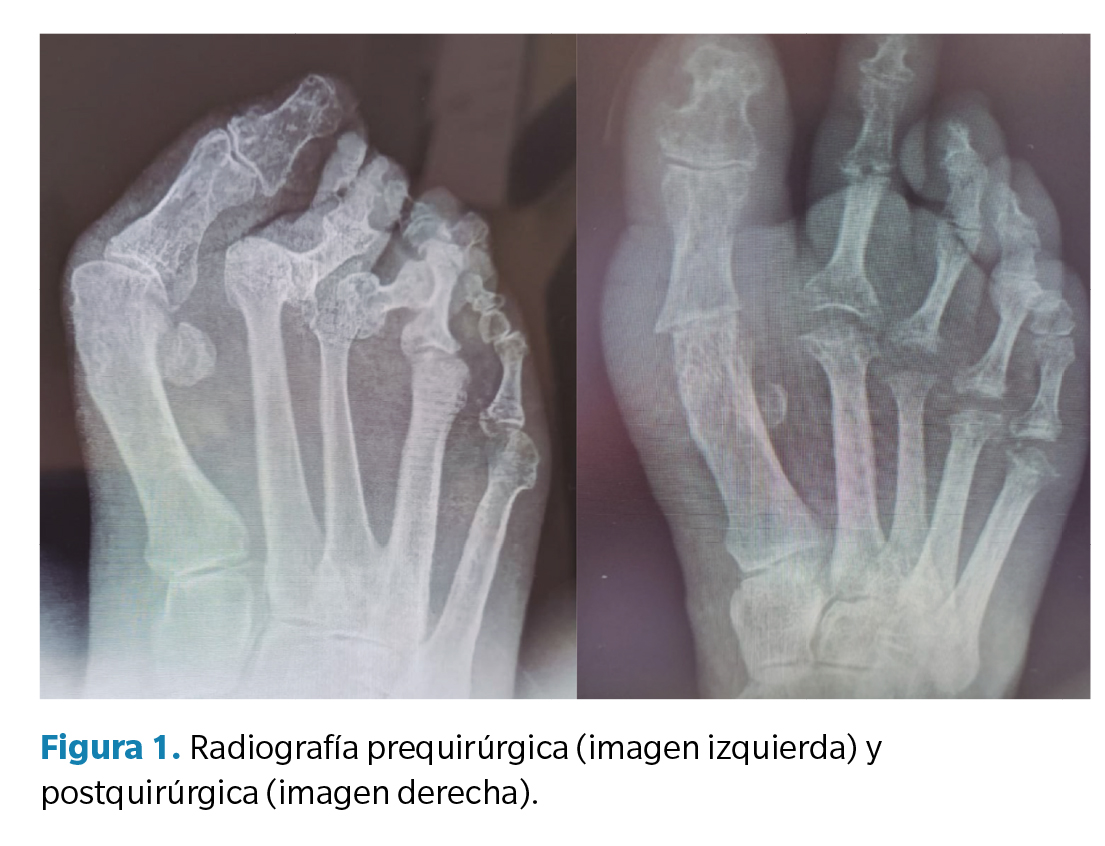

Previo a la recogida de datos, se llevó a cabo una anamnesis donde se recogieron variables genéricas (altura, peso, índice de masa corporal y lateralidad), categorización del riesgo quirúrgico (escala ASA), categorización del riesgo de trombosis venosa profunda (escala Autar), escala SF-36, escala AOFAS, motivo de consulta y valoración clínica del dolor (escala EVA). La valoración preoperatoria consistió en una exploración clínica, donde se observó la deformidad, tanto en carga como en descarga, y se llevaron a cabo diversas maniobras para valorar los rangos articulares de movimiento, prestando atención a la localización de dolor y/o de distintas hiperqueratosis asociadas a la deformidad. Asimismo, se llevó a cabo un estudio vascular en el que se palparon los pulsos pedio y tibial posterior acompañado de un eco-doppler y el índice de pie y tobillo (índice T/B). Además, se realizó un estudio biomecánico de la marcha, tanto baropodométrico como dinámico y, finalmente, se llevó a cabo un estudio radiológico (Figura 1) del pie a intervenir.

Junto con estas escalas, también se realizó un análisis radiológico de la deformidad en la Rx dorsoplantar en carga, donde se valoraron los siguientes ángulos: ángulo intermetatarsal, ángulo de hallux abductus valgus, ángulo de Merchan y ángulo interfalángico del hallux. Esta medición se realizó en la Rx preoperatoria y en la Rx postoperatoria al año de la intervención.

En cuanto a los ángulos radiológicos prequirúrgicos, se observa una media preoperatoria de 18.3º respecto al ángulo intermetatarsal I-II (IMA I-II) y de 48.4º respecto al ángulo hallux abductus valgus (αHAV). Tras la intervención, la media del IMA I-II fue de 15º y del αHAV de 24.1º. Respecto al ángulo de Merchan, se observa una media de 141.7 pretratamiento y de 141.6 postratamiento. En el caso del ángulo interfalángico, se obtiene una puntuación media de 5º pretratamiento y de 3.3º postratamiento (Tabla 3).